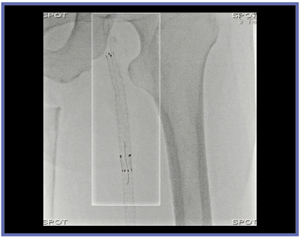

新しく開発されたスポット透視は,X線を照射したい関心領域を設定すると,その部分のみを透視し,関心領域以外は直前の透視のラストイメージホールド画像を表示することができる(図3)。全面透視とスポット透視の切り替えは,フットスイッチのペダルの踏み替えでできるため,術者の手技を妨げることがない(図4)。関心領域の設定は,マウスを使って透視モニタ上に現れる領域を移動,大きさ指定を行うだけで容易である。図5は,下肢動脈造影でステント内に再狭窄が認められた症例である。透視で見たい領域はステント部分だけであるため,スポット透視にすることで白い枠内だけに照射し透視画像を得て,周囲にはホールド画像を表示する。特に経皮的血管形成術(PTA)などは,関心領域の周囲は動かないためホールド画像で問題なく,スポット透視は良い適応と言えるだろう。

図5 スポット透視(5pps 低線量モード使用)